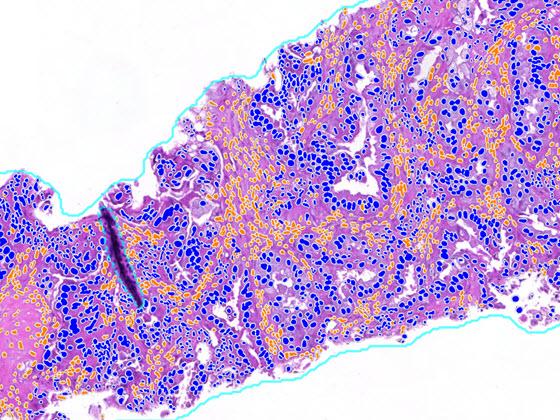

H&E digital slide (left) with Lung Macrodissection AI markup (right) displaying the tumor cell density heatmap.

After selecting an image, view the H&E slide in the viewer and the Lung Macrodissect AI results. Results include overlays and quantitative results. The first set of overlays prepare the tissue for analysis by identifying areas of analyzable tissue. The next overlay identifies areas of tumor in the tissue, with the tumor density heatmap highlighting the densest areas of tumor. With the assistance of the heatmap, users identify the dissection area by drawing a region of interest with immediate quantitative feedback on the number of all cells and tumor cells in the region to ensure proper sampling.